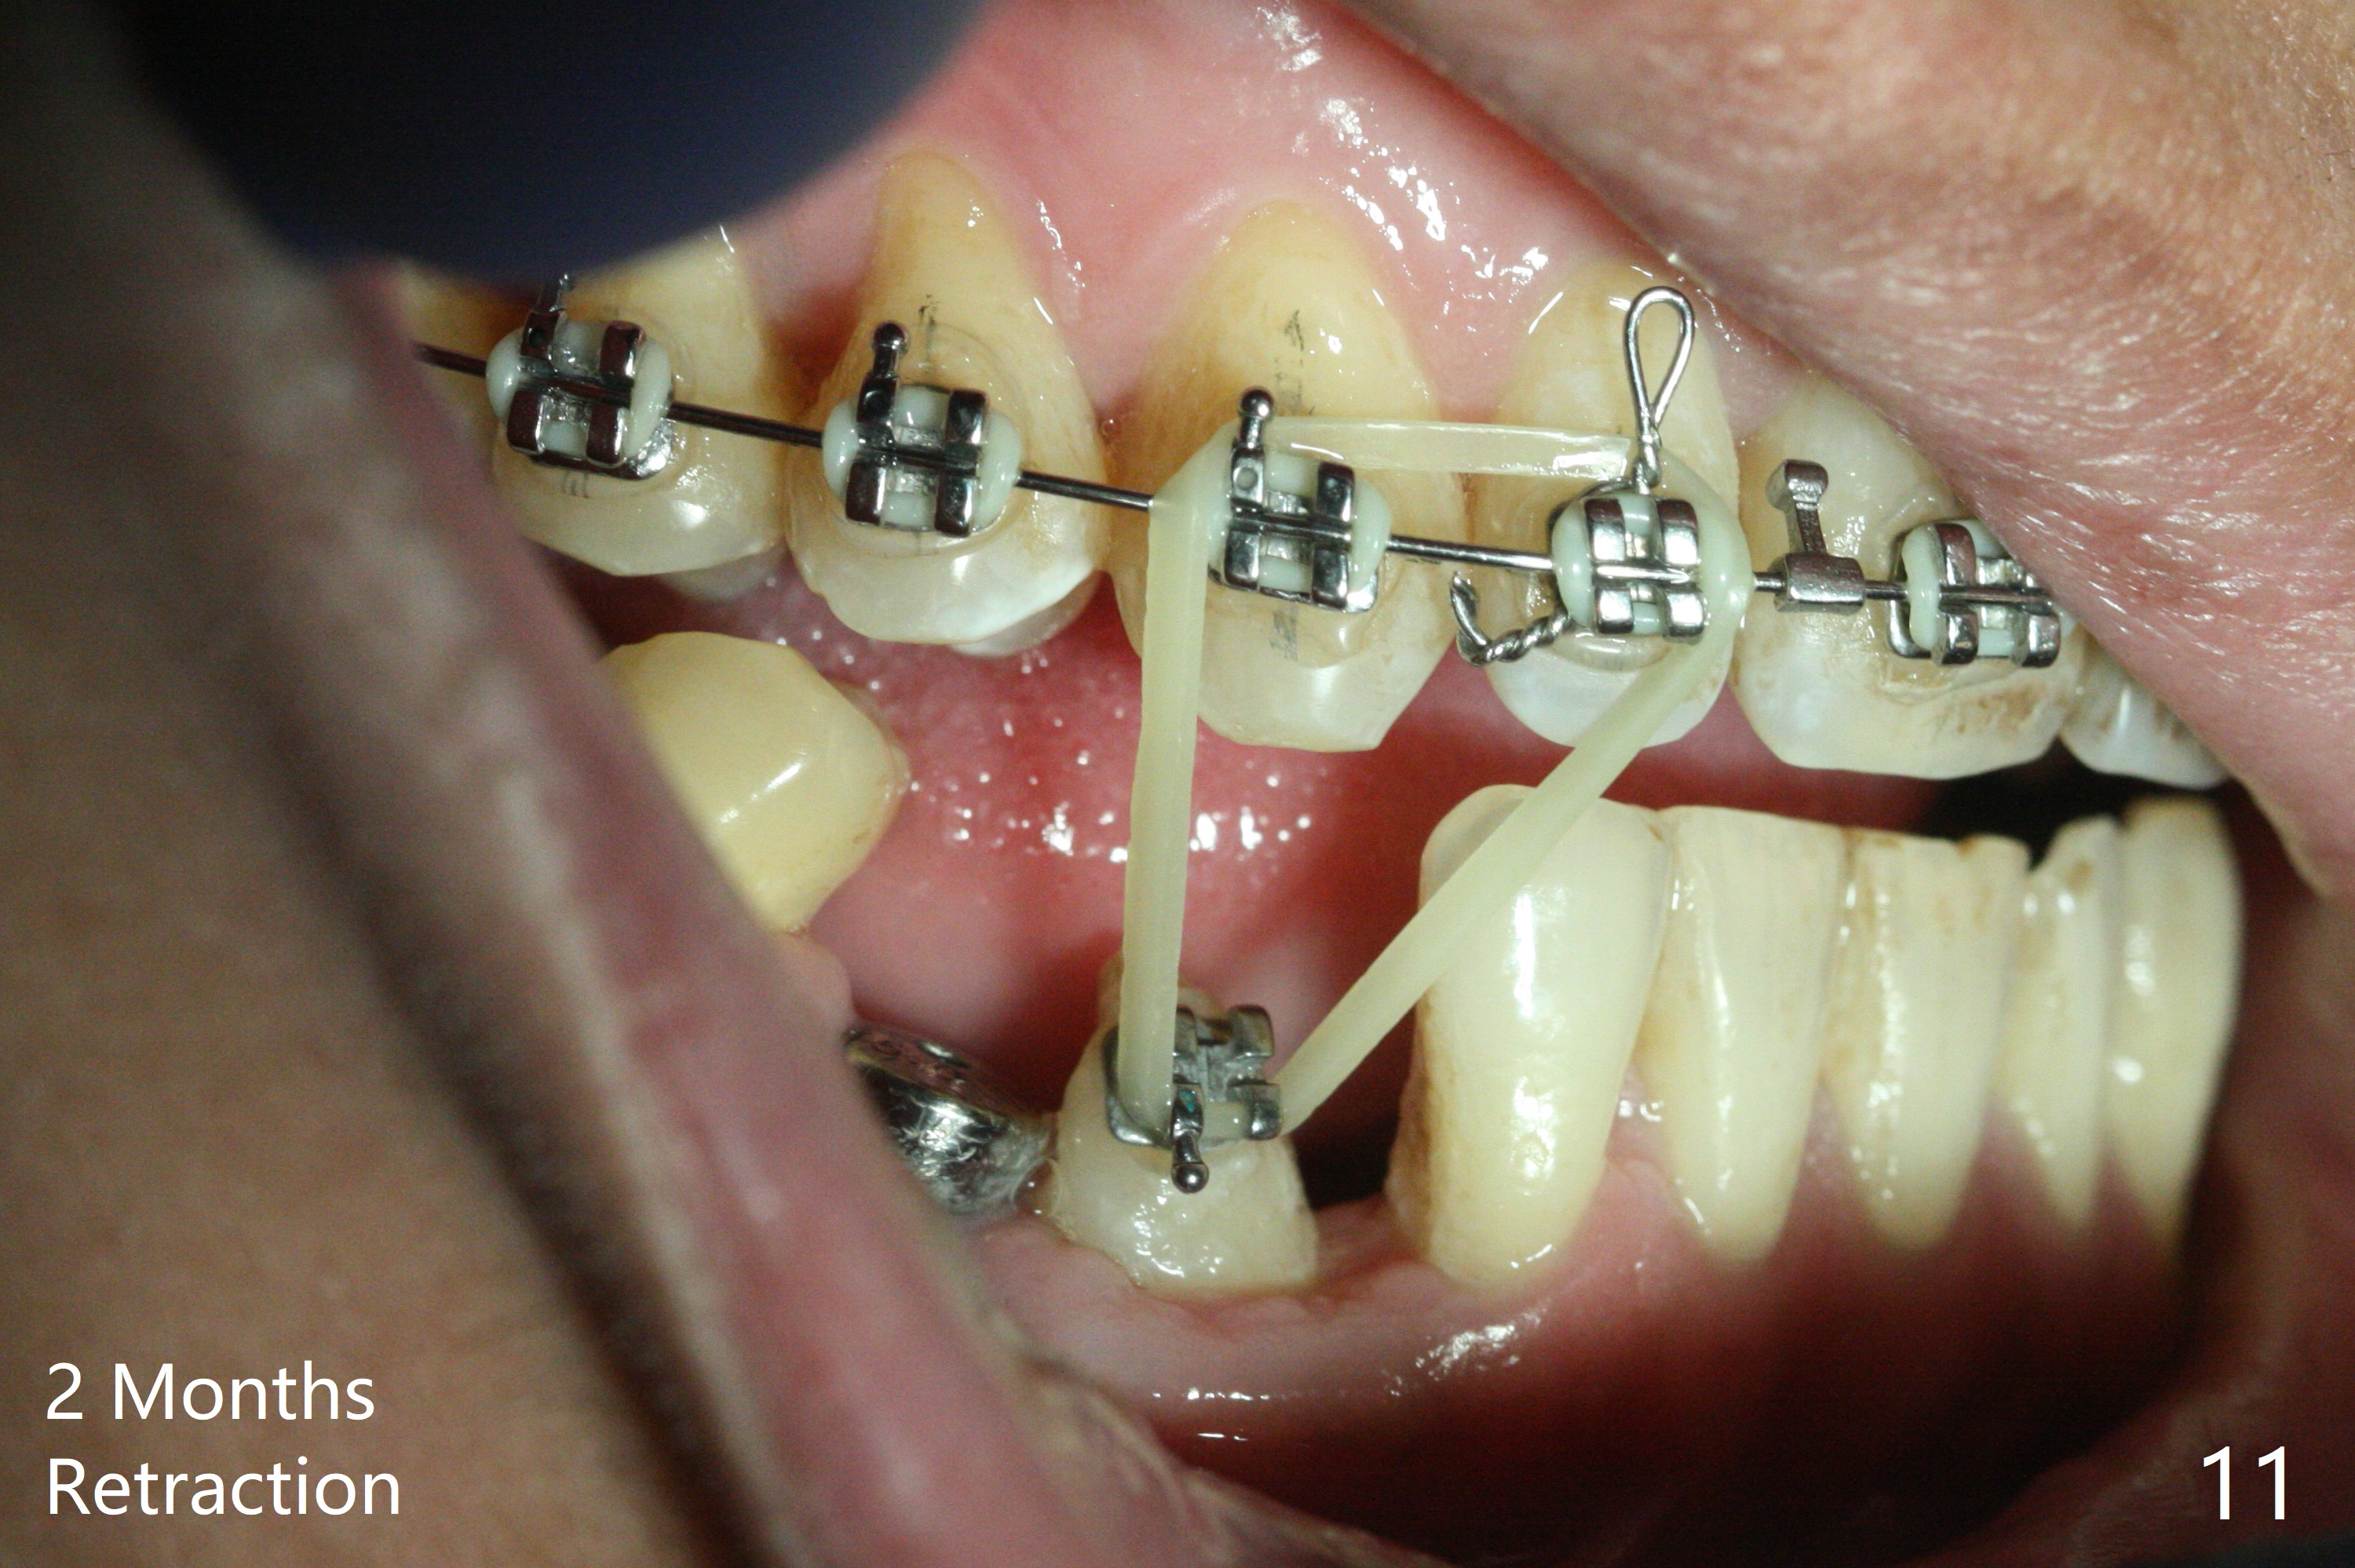

When the surgical guide for #28 is removed, the 4x13 mm implant is found to be superficial and buccal. Part of the buccal mucosa is nonkeratinized. After 1 mm deeper placement of the implant, CT confirms the buccal placement (Fig.1, as compared to design). In fact the guide was doubly checked for fitness prior to osteotomy, but grossly it seemed to be seated properly. The suspicion is related to the trimming at the site of #27 (Fig.2,3 (*), as compared to a mounted model in Fig.4,5 (arrowhead) and the model sent to lab for guide fabrication). The lab agrees to redesign the case. There is a narrow buccal band 1 week postop (Fig.6). The patient is a smoker. The implant was placed buccal (Fig.7, 1 month postop). A new 4x13 mm implant is placed on the top of the 1st line following 3x14.5 mm drill (Fig.8 (35 Ncm)). In fact the implant position is not changed much. Four months post banding (20 ss) and 2 months post 2nd implant placement, the tooth #27 is exposed for bracket; extrusion is initiated (Fig.9). In 3 weeks of retraction, the bracket is supragingival (Fig.10). The canine contacts the distal healing abutment with 2 months of retraction (Fig.11). It seems necessary to initiate lower bracket placement. There is no bone loss 4 months postop (Fig.12). A 4.5x7(4) mm abutment is placed (Fig.13) for a temporary crown as an anchor (Fig.14) to further extrude #27 with continuous inter-arch retraction (to reduce tension upon #26 with severe bone loss (Fig.12)). LR3 extrusion is incomplete, although there is an increase in bone distal to LR2 ~ 10 months of extrusion (Fig.15).